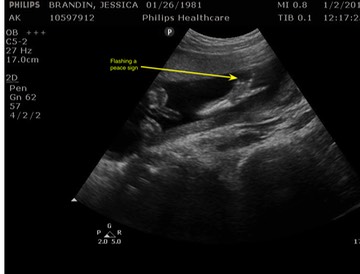

An Early Sonogram—gender not to be seen, but catch the fingers and the V-sign